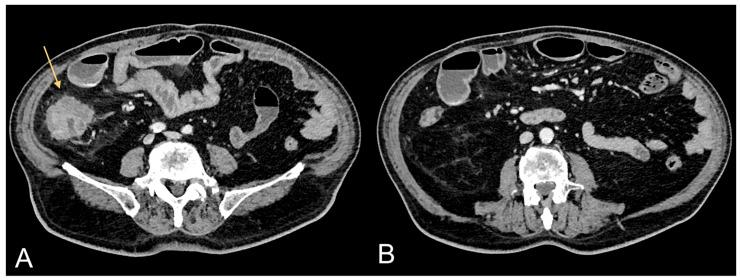

Obesity is an established risk factor for cancer. However, conventional measures like body mass index lack precision in assessing specific tissue quantities, particularly of the two primary abdominal fat compartments, visceral adipose tissue (VAT) and subcutaneous adipose tissue (SAT). Computed tomography (CT) stands as the gold standard for precisely quantifying diverse tissue types. VAT, distinguished by heightened hormonal and metabolic activity, plays a pivotal role in obesity-related tumor development. Excessive VAT is linked to aberrant secretion of adipokines, proinflammatory cytokines, and growth factors, fostering the carcinogenesis of obesity-related tumors. Accurate quantification of abdominal fat compartments is crucial for understanding VAT as an oncological risk factor. The purpose of the present research is to elucidate the role of CT, performed for staging purposes, in assessing VAT (quantity and distribution) as a critical factor in the oncogenesis of obesity-related tumors. In the field of precision medicine, this work takes on considerable importance, as quantifying VAT in oncological patients becomes fundamental in understanding the influence of VAT on cancer development-the potential "phenotypic expression" of excessive VAT accumulation. Previous studies analyzed in this research showed that VAT is a risk factor for clear cell renal cell carcinoma, non-clear cell renal cell carcinoma, prostate cancer, and hepatocarcinoma recurrence. Further studies will need to quantify VAT in other oncological diseases with specific mutations or gene expressions, in order to investigate the relationship of VAT with tumor genomics.

肥胖是一种公认的癌症风险因素。然而,诸如体重指数等传统测量方法在评估特定组织量时缺乏精确性,尤其是对于两个主要的腹部脂肪腔室,即内脏脂肪组织(VAT)和皮下脂肪组织(SAT)。计算机断层扫描(CT)是精确量化各种组织类型的金标准。VAT以其较高的激素和代谢活性为特征,在肥胖相关肿瘤的发展中起关键作用。过多的VAT与脂肪因子、促炎细胞因子和生长因子的异常分泌有关,促进了肥胖相关肿瘤的致癌作用。准确量化腹部脂肪腔室对于理解VAT作为肿瘤学风险因素至关重要。本研究的目的是阐明用于分期目的的CT在评估VAT(数量和分布)作为肥胖相关肿瘤发生的关键因素方面的作用。在精准医学领域,这项工作具有相当重要的意义,因为在肿瘤患者中量化VAT对于理解VAT对癌症发展的影响——过多VAT积累的潜在“表型表达”变得至关重要。本研究分析的先前研究表明,VAT是透明细胞肾细胞癌、非透明细胞肾细胞癌、前列腺癌和肝癌复发的风险因素。进一步的研究需要在具有特定突变或基因表达的其他肿瘤疾病中量化VAT,以便研究VAT与肿瘤基因组学的关系。